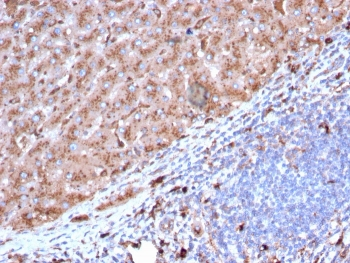

Cathepsin D Antibody

| Description | Cathepsin D Antibody |

| Tested applications | FC, ICC, IHC, IP, WB |

| Reactivity | Human, Mouse |